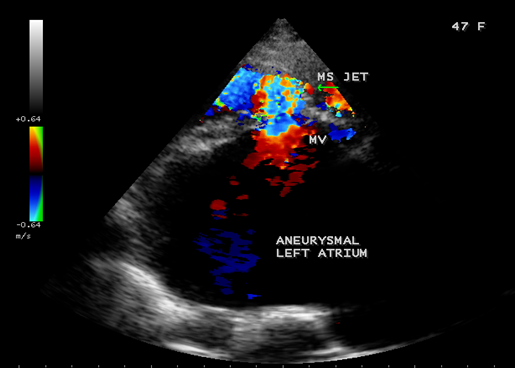

Case 4. Giant left atrium in mixed rheumatic mitral valve disease- both mitral stenosis and regurgitation as shown in Figures 15 to 20 in a 47-year-old female. The patient was advised lifelong penicillin prophylaxis, MVR (mitral valve replacement), LA volume reduction surgery with Cox-Maze procedure for atrial fibrillation.

Figure 19. Parasternal long axis view showing the severe mitral regurgitation and giant left atrium in a 47-year-old female.

Figure 20. Parasternal long axis view showing the mitral stenosis jet and giant left atrium in a 47-year-old female.

The balloon-like enlargement of the left atrium which occupied the whole of the posterior, right and left mediastinum and the rest of the heart looks like a ‘crown on a cushion’ as shown in Figures 17 and 18 in mixed mitral valve disease (both stenosis and regurgitation) as in Figures 19 and 20.